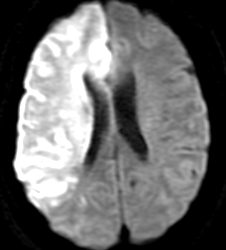

MRI;拡散強調画像

【MRI;拡散強調画像】

MRIでは1.5cm以下の小さな梗塞として描出。